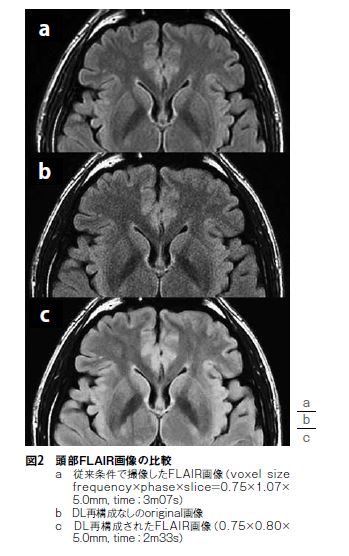

AIR™ Recon DLの特長として主に①ノイズの劇的な低減によるsignal-to-noise ratio(SNR)の向上、②空間分解能の向上、③トランケーションアーチファクトの低減が挙げられる。これまでの様々な高速化技術やフィルター処理等の経験則から、「ノイズ低減によるSNR向上技術」と聞くとSNRの向上に反して、空間分解能の低下やコントラストの低下が生じるのではないか?と疑いを持つかもしれない。しかし、AIR™ Recon DLを使用することによる上記のような懸念は無く、SNRの高い、非常に鮮明なMR画像を得ることが可能である。AIR™ Recon DL再構成は従来再構成のようにフーリエ変換を介さず、raw dataから直接畳み込みニューラルネットワークを介して、MR画像を再構成する(図1)。現仕様では、2D撮像のみの対応となっており、DL再構成によるdenoising levelはLow、Medium、Highの3段階で調整可能である。また、比較のためにDL再構成処理なしのoriginal画像も出力可能となっている(図2)。再構成に費やす時間も従来再構成と比較して遜色なく、「画像がなかなか出てこない!」といったようなストレスを感じることなく業務を遂行できる。

AIR™ Recon DLは現在2Dのみの対応ではあるが、spin echo(SE)系、gradient echo(GRE)系、diffusion weighted image(DWI)、FIESTA、single-shot fast spin echo(SSFSE)の幅広いコントラスト・撮像法に対応している。当院の運用として、AIRTM ReconDLによってSNRに余裕が生まれるため、最短echo spaceになるよう受信バンド幅を調整しつつ、収集ボクセルサイズを検査全体で平均約35%向上させた。さらにAIR™ Recon DL自体にも鮮鋭度を向上させる効果(従来再構成よりも約30%鮮鋭度が向上)があるため、視覚的インパクトは想像以上である(図3)。体動やフローアーチファクトの影響無ければ、加算回数(NEX)を積極的に減らすことができるため、撮像時間の短縮に繋がる。急に画質が良くなりすぎると逆に違和感を持つ人もいるかもしれないが、AIR™ Recon DLはdenoisinglevelを3段階調整可能なため、適度にノイズがのった鮮鋭度の高い画像を得ることもできる。